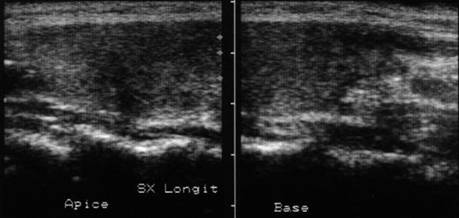

Femeie 25 ani. Nodul unic in lobul stang, contur net, hipoecogen, respecta parenchimul din jur, neomogen, de 18x23x36 mm (7,5 cc).

Citoaspiratia cu ac subtire: nodul adenomatos.

Examen histologic postoperator: adenom trabecular fetal.

Acelasi caz. La doppler color - vascularizatie interna, mai evidenta in powerdoppler.